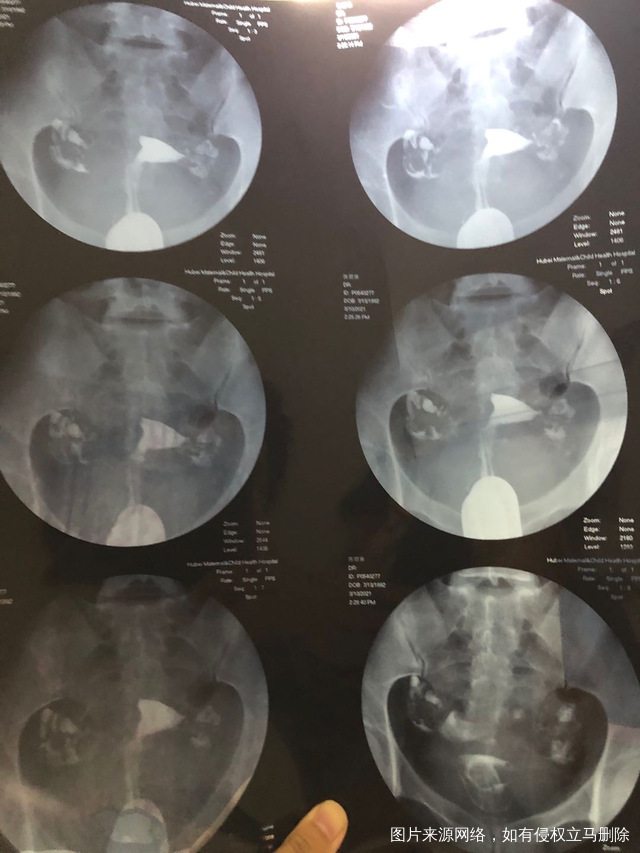

一子十岁隔年人流一次19年宫外孕保守治疗右侧